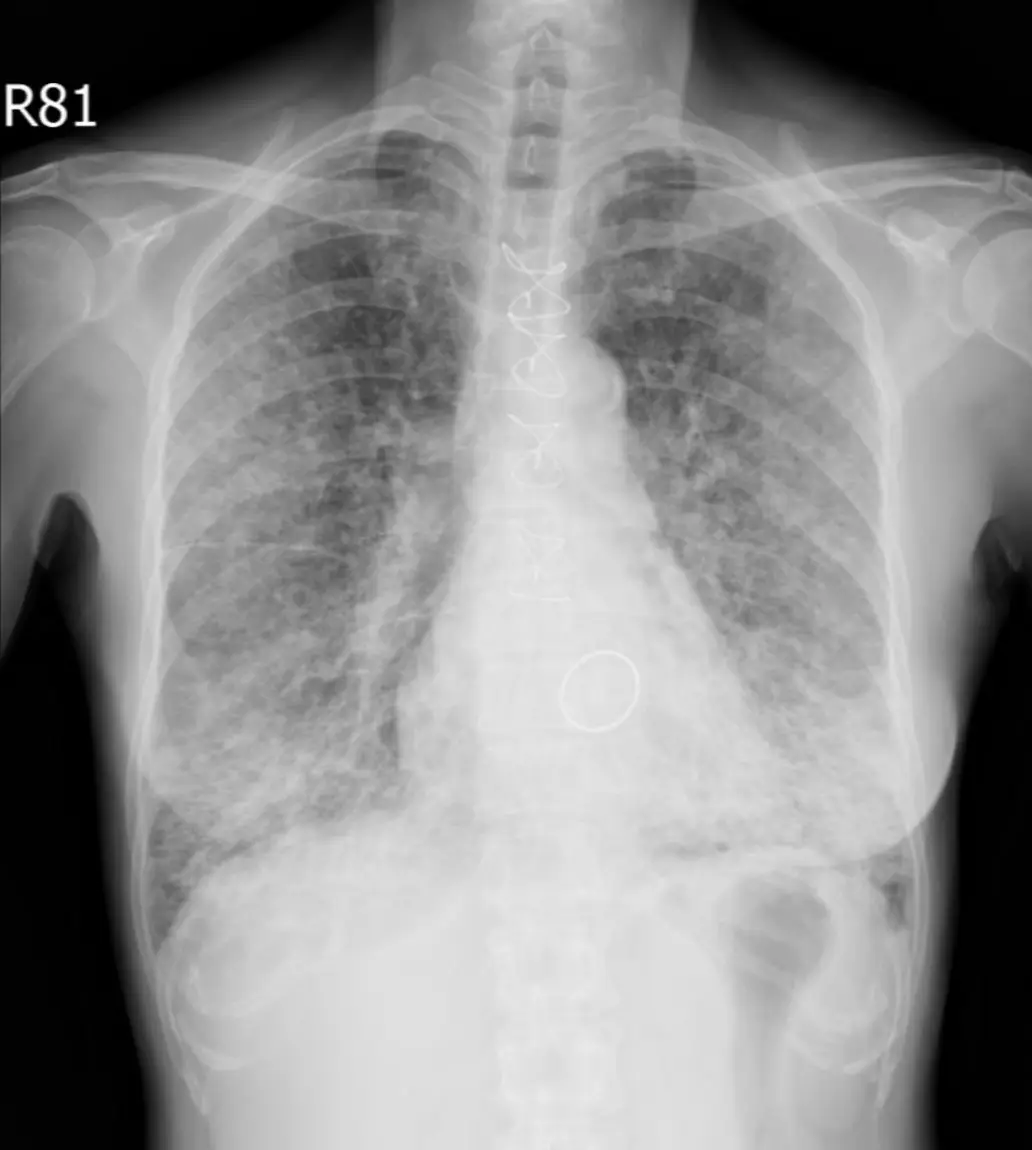

本題考查長期服用 Amiodarone(一種碘含量達 40% 的抗心律不整藥物)的病患出現喘氣加劇時,如何根據胸部 X 光(CXR)、胸部電腦斷層(CT)及腹部 CT 的綜合影像特徵,診斷「Amiodarone 誘發的間質性肺病(Amiodarone-induced interstitial lung disease, AILD)」並與其他間質性肺病做鑑別。

圖一(胸部 X 光,正面): 雙側肺野可見瀰漫性網狀-線條狀(reticular-linear)浸潤,以中下肺野為著,右側稍重於左側。可見明顯的間質性增厚線條,符合 Kerley B line 樣外觀,但分布更瀰漫,延伸至全肺野,不像單純心因性肺水腫侷限在下肺野。心臟左側可見金屬人工瓣膜(mechanical heart valve)的顯影縫環,符合病史中的二尖瓣換瓣手術。無局部實變(consolidation)、無明顯空洞或粟粒狀小結節。整體影像提示瀰漫性間質性病變而非局部感染。